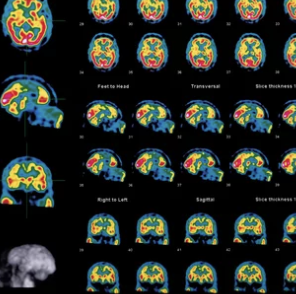

3. 도파민 운반체 스캔(DAT 스캔): 파킨슨병을 구별하는 핵심 검사

도파민 운반체 스캔, 즉 DAT 스캔은 파킨슨병을 진단할 때 매우 중요한 영상 검사로, 뇌 내 도파민 세포의 손실 여부를 확인하는 데 도움을 줍니다. 파킨슨병 환자는 도파민 세포가 감소해 있어 이 검사를 통해 파킨슨병과 다른 운동 질환을 구별할 수 있습니다.

DAT 스캔 검사 과정:

- 방사성 약물 주사: 도파민 수용체와 결합하는 방사성 약물을 주사하여 뇌의 도파민 수준을 촬영합니다.

- 영상 촬영: 약물이 흡수된 후, 특수 장비로 뇌를 촬영하여 도파민 세포가 감소했는지 확인합니다.

- 결과 분석: 도파민 수준이 낮다면 파킨슨병의 가능성을 높게 평가할 수 있습니다.

DAT 스캔은 파킨슨병을 구별하고 조기에 진단하는 데 매우 유용한 검사로, 특히 초기 증상이 모호한 경우에 효과적입니다.